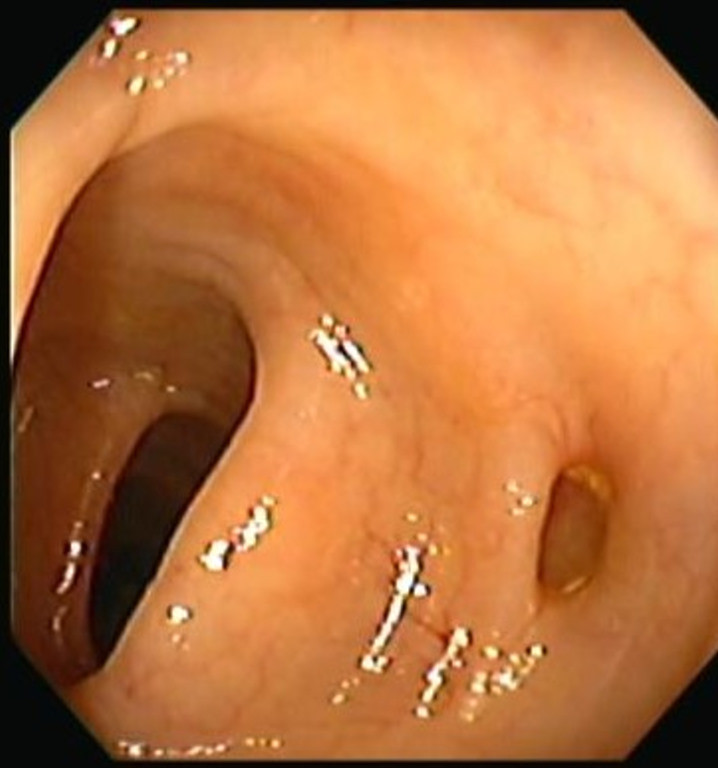

Enfermedad diverticular del colon

Envíado por Dr. Carlos Ernesto Arévalo